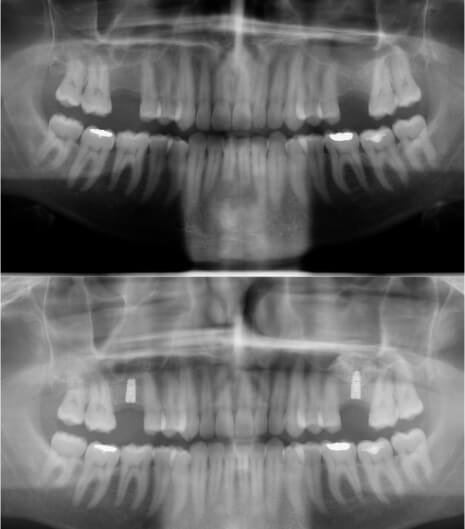

A hosszú ideig tartó foghiány és a rágás fizikai behatásának hiánya miatt a csont elveszti megtartó funkcióját: elvékonyodhat vagy felszívódhat

A csont adja a fogak és az implantátumok rögzítését. A csontot magát pedig a rágás mechanizmusa tartja meg. Így amikor foghiány keletkezik, és az elvesztett fog helyén megszűnik a rágás okozta fizikai behatás, akkor a csont elkezd vékonyodni, alacsonyodni, majd felszívódni, mivel funkcionális jelentősége már nincs.

Az alsó állcsontban többnyire a csont szélessége, a felsőben leggyakrabban a magassága szokott problémát okozni. Mindkét helyzetre vannak megbízható megoldások, amelyek hosszútávon tudják az odakerülő implantátumok stabilitását garantálni.